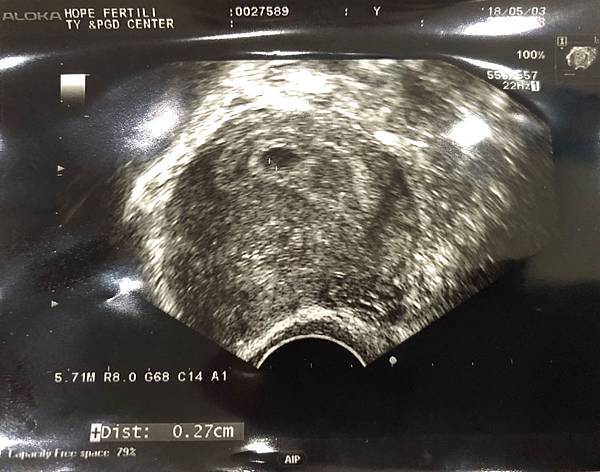

因為一直以來指數實在上升的太慢,所以每次回診我都想說『應該照不到了吧』,雖然很負面的心態,但是總覺得如果是不好的胚胎,一直留著好像也很強求。老是抱著負面的心態照超音波,就在第六週的今天,居然照到了胚胎,也照到像是心跳的一閃一閃著,照到時真的很感動,雖然又是比一般6週的大小來的小,但小小生命在肚子裡跳動著,那感覺很奇妙。就這樣又通過了一關,一直穩定的長大著。